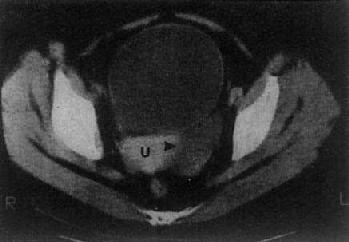

(三)卵巢囊肿或肿瘤 单纯的卵巢囊肿,大多是潴留囊肿,常较小,CT易于显示。表现为囊性低密度影,CT值接近水,边界光滑整齐,大小常为数厘米(图4-5-8)。囊性畸瘤表现为密度不均的低密度肿块,内含多种组织如脂肪、钙化、牙或骨组织皮样囊肿,其壁常有钙化。卵巢囊腺瘤常较大。浆液性囊腺瘤可为单房性或多房性,壁较薄,少数可为双侧性。粘液性囊腺瘤壁较厚,常为多房性。它们的CT值约为15Hu,增强扫描其壁和囊均不增强。卵巢恶性肿瘤表现为盆腔或下腹部肿块,呈软组织密度,CT值40~50Hu,肿瘤大多同时具有实性和囊性部分,边缘不规则,这些有别于良性囊腺瘤和单纯性囊肿,增强扫描实体部分有增强。卵巢癌可产生腹水,其CT值偏高,可达60Hu,30%的病例可见腹膜或大网膜转移,表现为前腹壁后方扁平形软组织肿块,密度不均,境界不清。有时可见腹膜、腹腔内及肠壁间结节肿块。CT检查了解卵巢癌的范围和转移情况比判断原发癌更为重要。

卵巢囊肿

图4-5-8 卵巢囊肿

子宫(U)左侧有一长圆形低密度区(→),边界清楚,其CT值与膀胱CT值相似